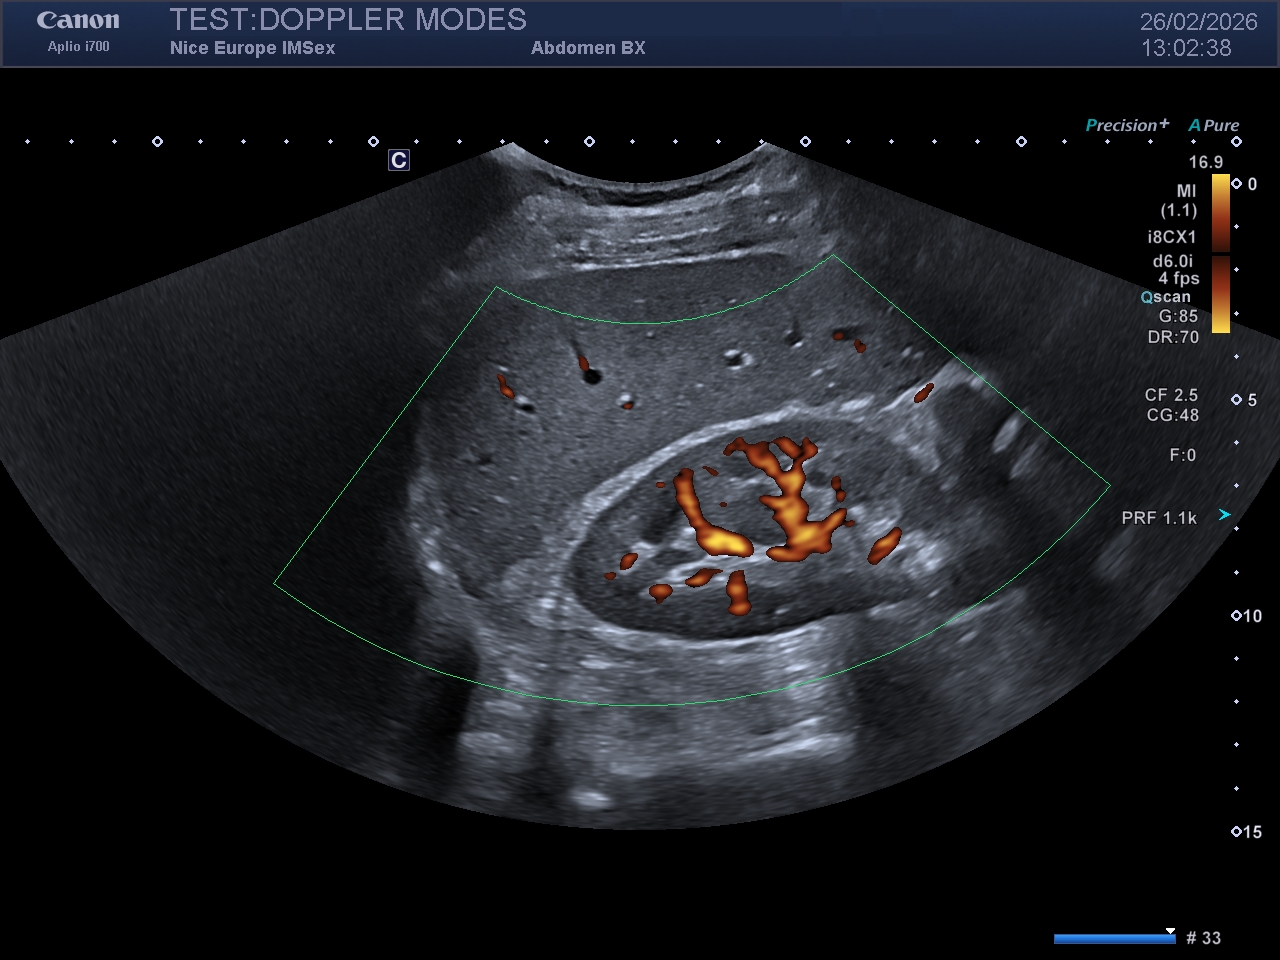

Légende : Image en Doppler Énergie du même rein droit. Notez la plus grande quantité de signal Doppler affichée sur l'image, mais aussi le caractère "grossier" de la cartographie couleur

Le Doppler énergie s'affranchit de l'analyse des décalages de fréquences pour se concentrer exclusivement sur l'intégrale (l'aire sous la courbe) du spectre de puissance du signal Doppler. Concrètement, il mesure la puissance du signal rétrodiffusé, qui est directement proportionnelle à la quantité d'hématies en mouvement dans le volume d'échantillonnage, indépendamment de leur vélocité ou de leur direction.

Sensibilité accrue : Le PDI présente un rapport signal sur bruit nettement supérieur au Doppler Couleur. Il détecte des flux beaucoup plus lents et des vaisseaux de plus petit calibre.

Indépendance angulaire relative : L'amplitude du signal n'étant pas régie par le cosinus de l'angle, le PDI permet de visualiser la perfusion de structures anatomiques tortueuses ou difficiles d'accès.

Moulage pariétal : En s'affranchissant du phénomène d'aliasing, il permet un excellent "moulage" des lumières vasculaires, révélant avec acuité les irrégularités pariétales ou les plaques d'athérome anéchogènes.

Inconvénient majeur : Il ne fournit aucune information hémodynamique directionnelle ou vélocimétrique, et se révèle très sensible aux artefacts de mouvement (flash artefacts) générés par la respiration ou les pulsations de l'opérateur et du patient.